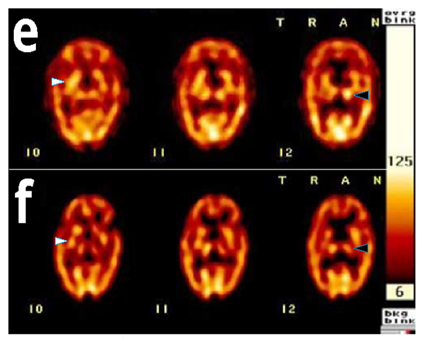

A 90‒year‒old, right‒handed female visited the gastrointestinal (GI) department of our hospital on October 28, 2005 with complaints of poor appetite and low grade fever. The patient was admitted to the GI ward under the impressions of ileus and pyuria. On November 18, 2005, the patient developed poor muscle power, right hemiplegia, and disturbed consciousness. Magnetic resonance imaging (MRI) of the brain revealed acute left side cerebral infarction Figure 1(A‒B) and an old lacunar infarction on the right side Figure 1(C‒D) Inpatient rehabilitation was arranged for neurological recovery. On December 21, 2005, the patient's caregiver noted prominent involuntary movement around the mouth similar to a rabbit's behavior. Upon inquiry, the patient revealed no previous psychiatric history and had never taken antipsychotic medication. On examination, a rhythmic lip‒oral movement was observed, and the frequency was measured to be 4 to 5Hz. However, the frequency of movement increased when she was stressed or distracted and decreased during voluntary activities such as talking. There was no involvement of the tongue, and lip‒oral movements were absent during the patient's sleep. We observed no abnormal movements anywhere else on the body. Based on these symptoms, a diagnosis of rabbit syndrome was made. An MRI study (on November 21) of the patient's brain produced unremarkable findings aside from the previous lesions. To further investigate the syndrome, the regional cerebral perfusion scan with an ethyl cysteinate dimer (ECD) single photon emission computed tomography (SPECT) SPECT scan of the patient's brain was performed, which revealed increased perfusion of the right basal ganglia and left thalamus Figure 1A & Figure 2A. The patient was prescribed the antiparkinsonian medication Madopar (levodopa/benserazide), 250mg bid (January 2‒9). After 7 days, the abnormal oral motions faded outré solved, the hemiplegia was mildly improved, and the other symptoms resolved resolved. Upon fade‒outre solution of the patient's symptoms after 7days, Madopar was discontinued, and one week later (January 23) we repeated the SPECT scan to reevaluate perfusion of the basal ganglia. Findings from the SPECT scan indicated that basal ganglia perfusion had returned to normal. Furthermore, the scans indicated decreased uptake in the left thalamus Figure 1F & Figure 2B. Once the patient exhibited relative recovery of muscle strength of her right limbs, she was discharged on January 23, 2006.

Figure 2 Brain single photon emission computed tomography images showed obtained during and after rabbit syndrome in our patient. A Iincreased uptake in the right basal ganglia (while arrow head) and left thalamus (black arrow head) during presentation of the rabbit syndromedisorder (E), and later after fade‒out, there were n. B. Normal uptake in the right basal ganglia and decreased uptake in the left thalamus were noted after resolution of the condition (F).

In this report, we describe an antipsychotic without naive patient with rabbit syndrome that was associated with increased basal ganglia and thalamic perfusion, as measured by SPECT. Rabbit syndrome is most commonly associated with prolonged exposure to antipsychotics. In a limited number of reports, rabbit syndrome has been described to result from a brain dysfunction, such as structural lesion or dysfunction in processing,3‒5 which three reports assumed that.3,4 In both cases, rabbit syndrome resembles parkinsonism. It is and it is thought that altered dopamine function in the basal ganglia underlies rabbit syndrome.7‒9 For example, in patients chronically exposed to antipsychotics, dopamine D2 receptor blockade is thought to lead to rabbit syndrome, thereby explaining extrapyramidal effects.9,10 Therefore, antiparkinsonian medication, which acts to boost dopamine levels, effectively treats rabbit syndrome. The Table 1 compares findings in our patient displaying rabbit syndrome with patients reported by prior three articles.3‒5 In each of these threewo previous reports, rabbit syndrome was not effectively controlled with antiparkinsonian drugs. Of them specifically, showed that anticholinergics and Levadopa were ineffective at treating the oral symptoms.3 Likewise, showed anticholinergics to be ineffective at treating rabbit syndrome in a patient thought to display the syndrome due to generalized brain dysfunction. However, only low doses of the anticholinergic were administered in this study.4 The Our patient described in the current case report had never received neuroleptics before symptom presentation. Moreover, we observed dramatic improvement in rabbit syndrome symptoms following administration of antiparkinsonian drug Madopar, which acts to increase dopamine levels in the brain. Therefore, this is the first description to our knowledge of an antipsychotic without naive patient with rabbit syndrome who was effectively treated with antiparkinsonian drug, similar to the well‒known treatment regimen for antipsychotic induced rabbit syndrome.1,2,5‒7 Interestingly, our SPECT findings revealed increased uptake in the right basal ganglia during the onset of rabbit syndrome, which decreased once the oral movement disorder faded out resolved. Our report shows a strong relationship between the onset of rabbit syndrome and basal ganglionbrain perfusion. Several studies have demonstrated abnormal basal ganglia function in a variety of conditions, such as pain traumatic brain injury and various posture and movement disorders.11‒20 Extrapyramidal movement disorders, such as Huntington's chorea, Parkinson's disease and rabbit syndrome, have been described to involve decreased perfusion of the basal ganglia.21,22 In contrast, increased perfusion of the basal ganglia has been described in patients with schizophrenia, especially in those with auditory hallucinations,13 but it has never been described in patients with rabbit syndrome. To the best of our knowledge, this is the first report to describe increased uptake in the basal ganglia upon presentation of rabbit syndrome. However, these findings need to be corroborated by further case reports.

The mechanism responsible for antipsychotic‒induced rabbit syndrome is thought to involve dopamine receptor blockade in the basal ganglia.8 Furthermore, one study showed decreased basal ganglia perfusion by SPECT in a patient displaying rabbit syndrome.23 In contrast, increased perfusion of the basal ganglia has been described in patients with schizophrenia, especially in those with auditory hallucinations,24 but it has never been described in patients with rabbit syndrome. To the best of our knowledge, this is the first report to describe increased uptake in the basal ganglia upon presentation of rabbit syndrome. Another interesting thing is the role of thalamus, the first SPECT findings revealed increased uptake in the left thalamus during the onset of rabbit syndrome, which decreased after administration of L‒DOPA. One of substructures of basal ganglion, substantia nigra pars reticulate, has been thought to be involved in the pathophysiology of rabbit syndrome.8 Animal studies have been confirmed a direct connection between substantia nigra pars reticulate and thalamus.25,26 A simple modulation of nigral activity may induce β‒band activity in the thalamus.26 We believe that the regional cerebral blood flows in thalamus positively responds to those of basal ganglion,27 e.g. simultaneously increasing or decreasing in both structures. However, these findings need to be corroborated by further case reports.